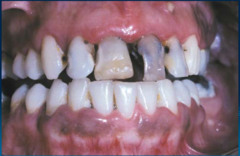

Meth mouth

Front

-generalized extensive destruction of tooth surface -meth use